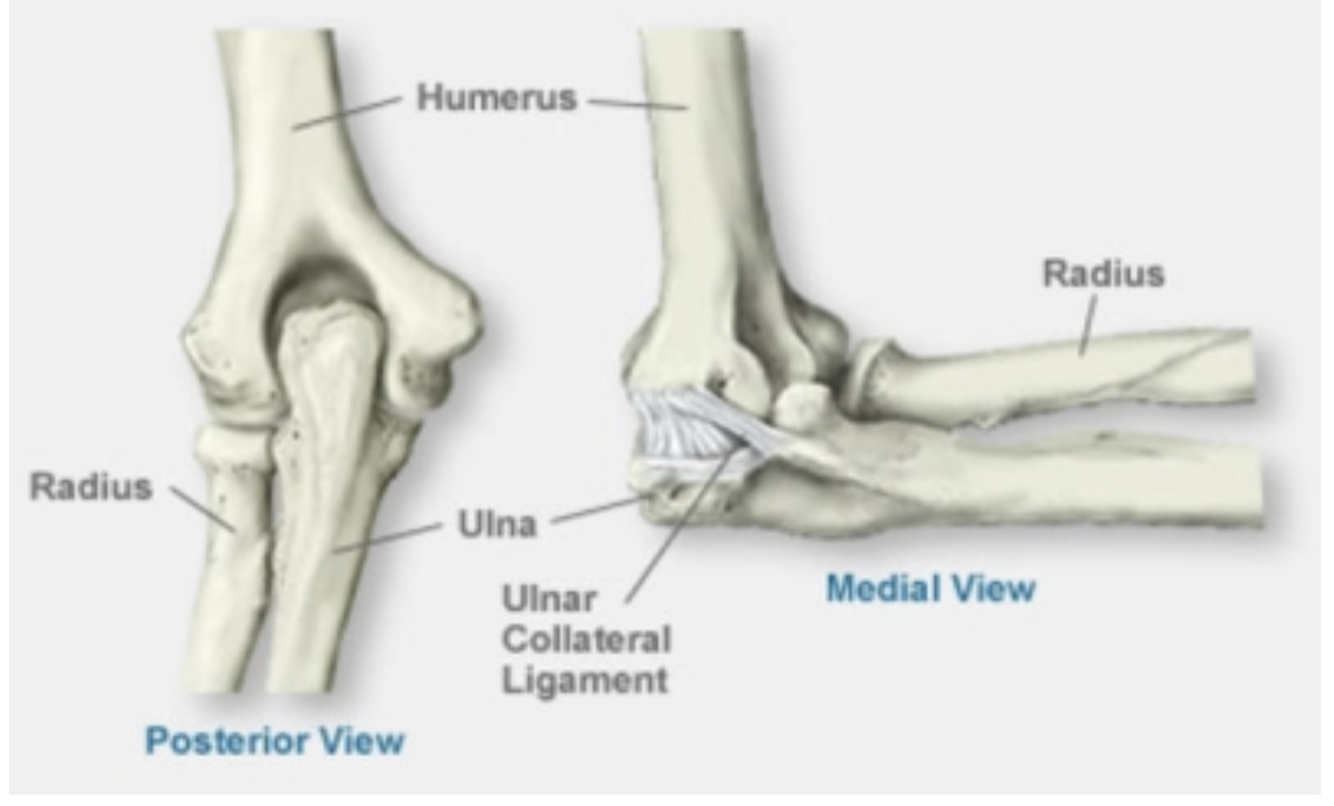

Ulna is bigger proximally, radius is bigger distally. Radius rotates, ulna doesn’t. The bones are held togeher by two radio-ulnar joints, proximally and distally.